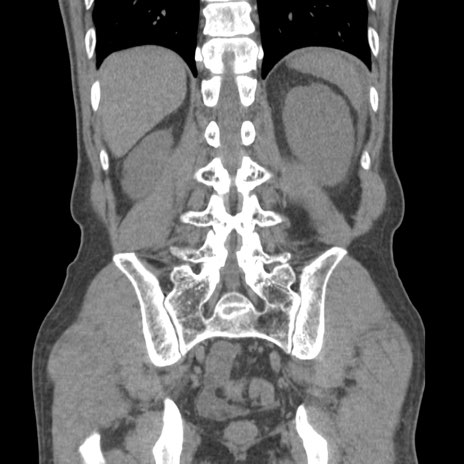

症例56 CT(冠状断像)